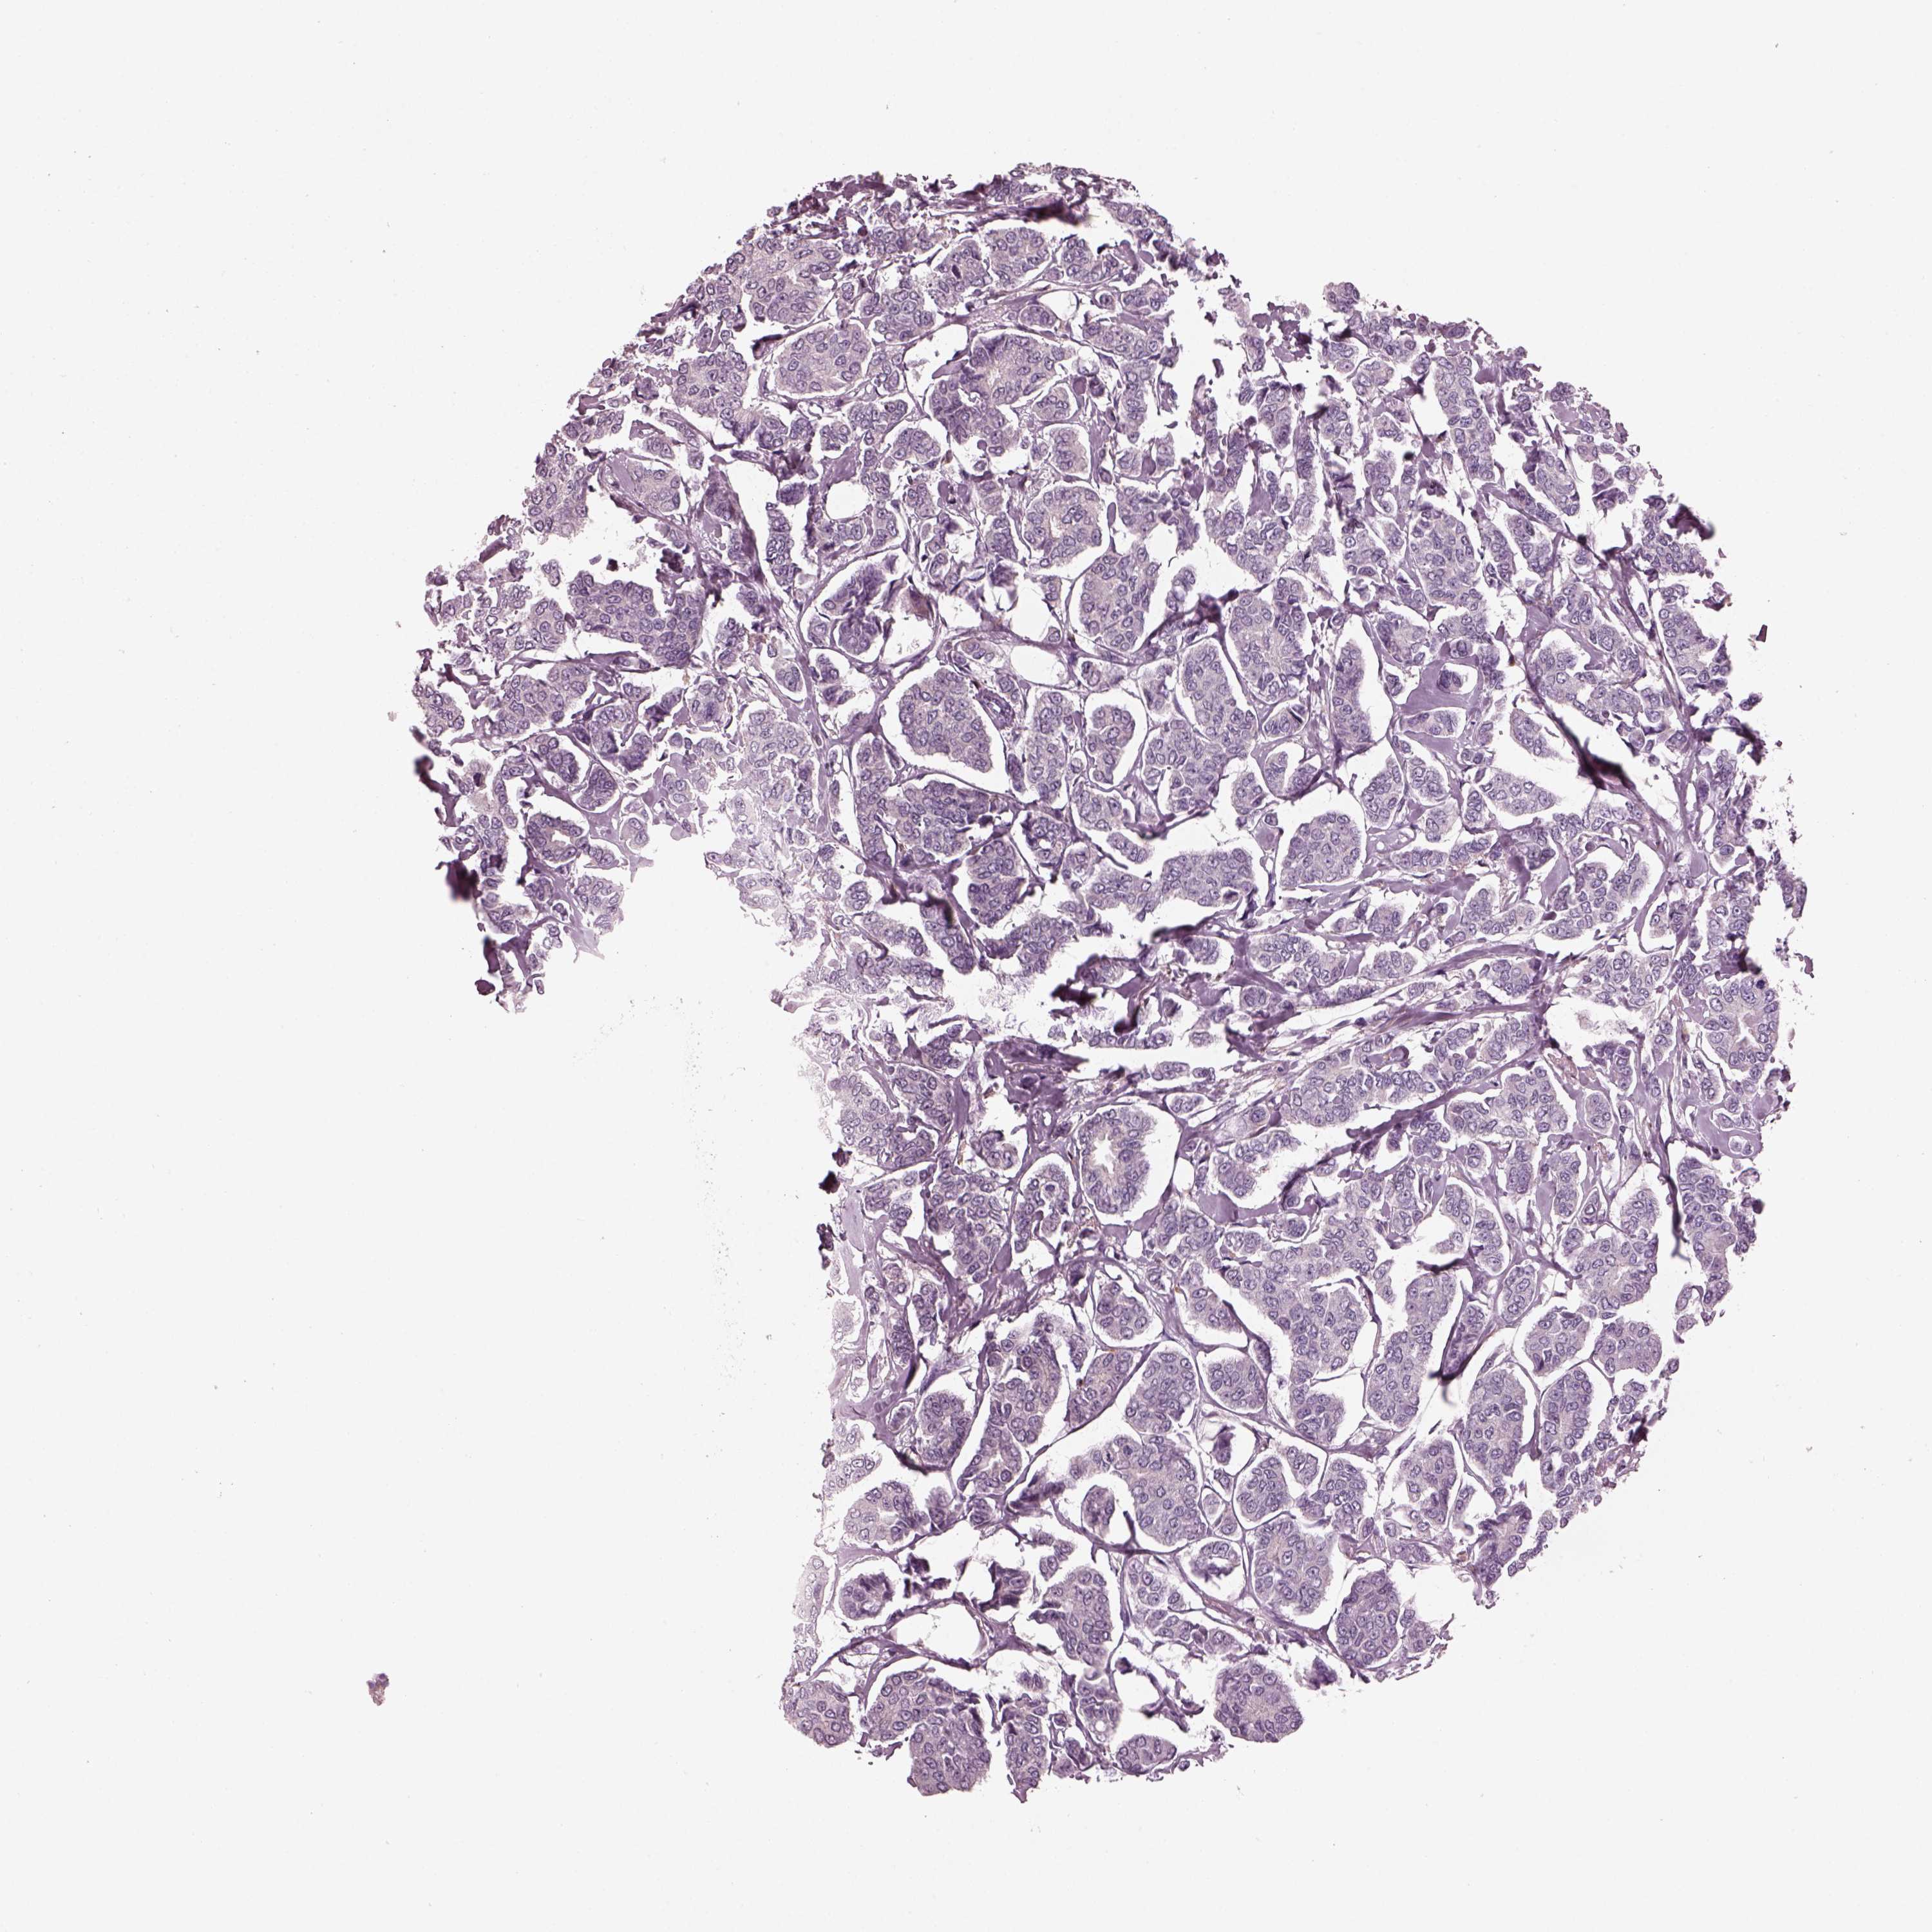

CANCER BREAST CANCER Show tissue menu

BRCA TCGA BRCA VALIDATION PROTEIN EXPRESSION

Breast cancer

Human cancer